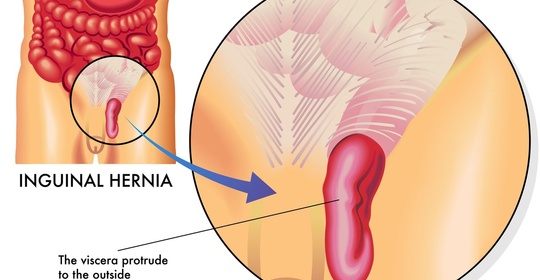

小兒疝氣:成因、症狀與治療,守護孩子健康